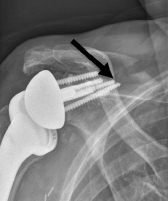

12 of the 21 scapular spine fractures occurred at the distal tip of the superior baseplate screw.

Comment: Scapular spine fracture is another of the complications of reverse total shoulder that are not seen with other types of shoulder arthroplasty. This study indicates that this complication is associated with the weakening of the spine from drill and screw penetration. The risk would seem to be increased by inferior angulation of the base plate and by the use of long drills and screws in the superior hole of the baseplate.